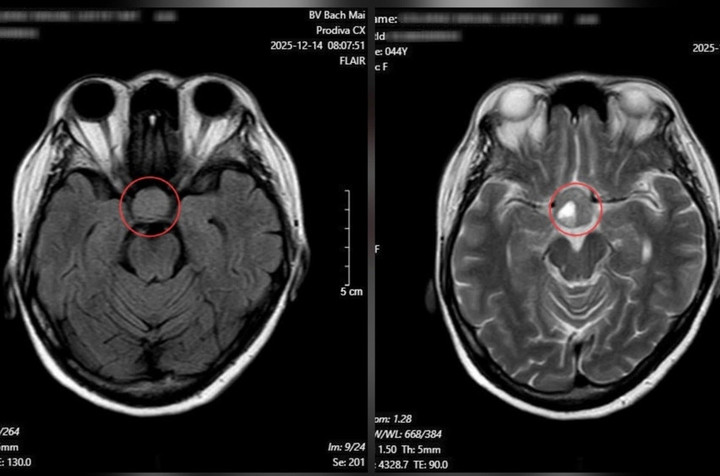

Kết quả chụp cộng hưởng từ (MRI) sọ não cho thấy khối u tuyến yên kích thước lớn.

Từ những dấu hiệu ở mắt, bệnh nhân được chỉ định chụp cộng hưởng từ (MRI) sọ não. Kết quả cho thấy một khối u tuyến yên kích thước lớn (macroadenoma), đo được 26 × 21 mm, đã chèn ép giao thoa thị giác. Người bệnh sau đó được chuyển sang chuyên khoa Phẫu thuật Thần kinh để tư vấn và lên kế hoạch điều trị, nhằm tránh nguy cơ mất thị lực vĩnh viễn và các biến chứng nặng nề khác.